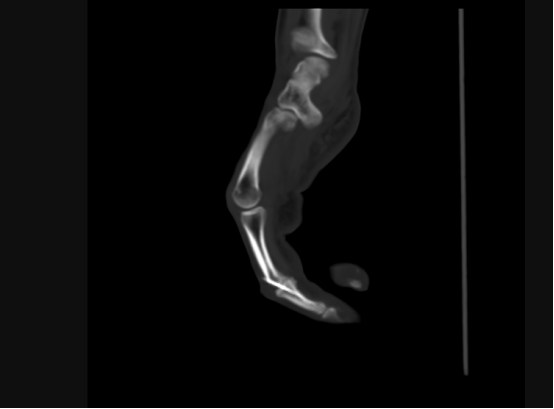

手術CT圖

“所謂自體關節移植,就是將患者自身的關節進行移植和替換,相比傳統的人工關節置換,該技術具有修復及時、沒有排異反應、治愈效果明顯等優點。”主刀醫生胡明興介紹,經放射醫學科行三維CT精準動靜脈及骨重建,在麻醉科的大力支持下,通過將腳趾關節及附近血管、神經、肌肉進行移植,他們僅用一次手術就為患者完成了手指修復,不需要多次開刀,盡可能保障了患者安全。